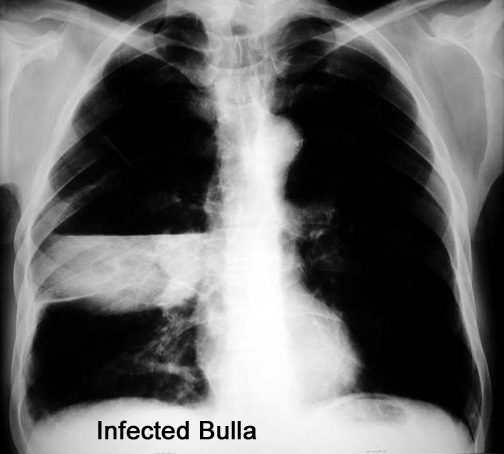

Case 1 Labeled Image What are the conditions where you get thin walled cavities?